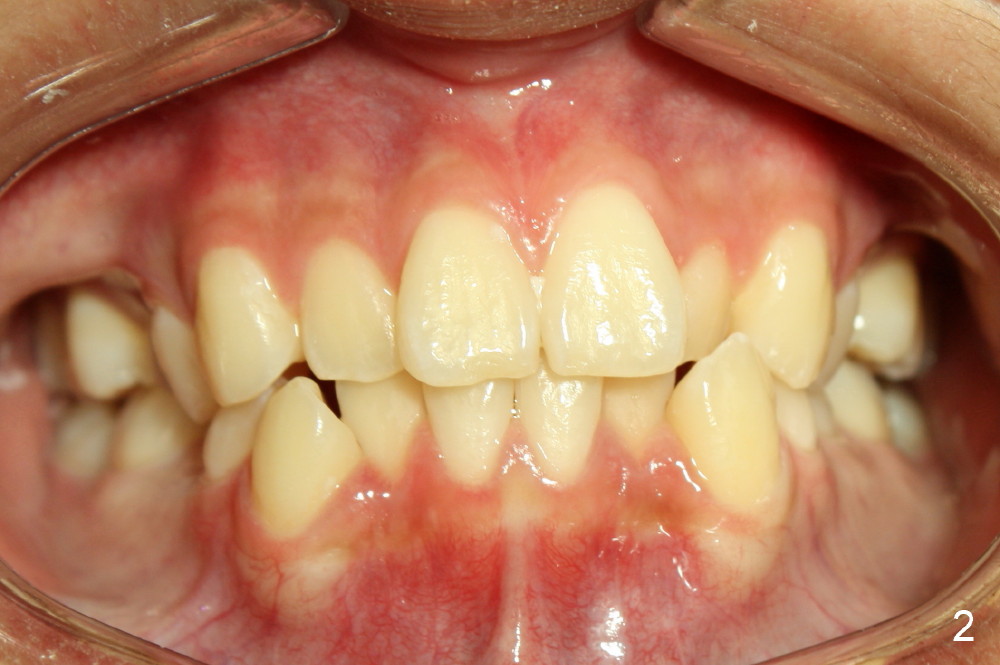

A 13-year-old boy has severe crowding (Fig.1-5). Four of the first bicuspids were extracted on 02/17/2014. Full mouth brackets or bands (except #18) were placed on 03/27/2014. Alignment improved 2 months later (Fig.11, 05/24/2014). The upper 18 ss wire was modified (Fig.12), and fixed with alastiks (Fig.13,14). One month later (07/01/2014), local alignment also improved (Fig.15); the upper modification is confined to one tooth.